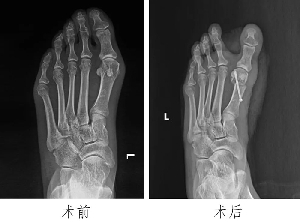

足踝外科:微創(chuàng)技術(shù)顯身手,造?;颊叱⊥?/a>

近年來(lái),微創(chuàng)技術(shù)在外科領(lǐng)域應(yīng)用日益廣泛。微創(chuàng)技術(shù)通過特殊的手術(shù)入路,應(yīng)用特殊的器械設(shè)備,比傳統(tǒng)方法創(chuàng)傷更小、精準(zhǔn)度更高,具有創(chuàng)口小、疼痛輕、出血少、恢復(fù)快、住院時(shí)間短等優(yōu)勢(shì)。我院足踝外科成立以來(lái),通過讓年輕醫(yī)生走出去、請(qǐng)進(jìn)來(lái)等舉措,學(xué)習(xí)引進(jìn)多種技術(shù),在科主任潘維亮的指引下,像徐潭潭、范明生、張亞州等